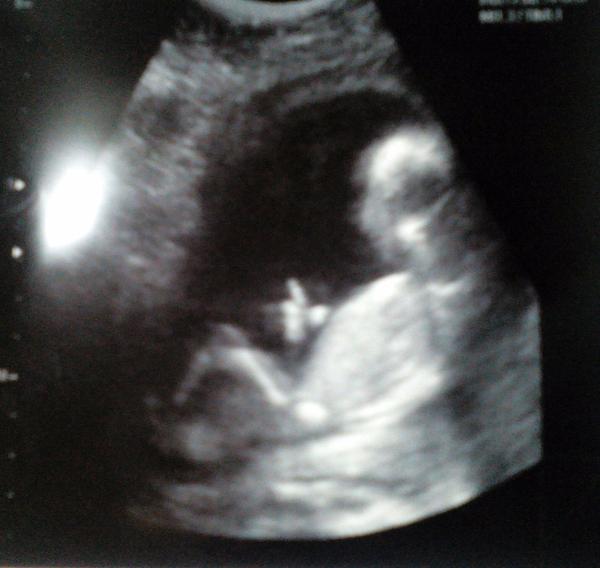

Fotka je zachycena v letu- mimi zrovna delalo kotrmelce, ale dokaze nam palcem nahoru vyjadrit, jak je stastne, ze nas zase dobehlo a neukazalo, co vlastne je 😂